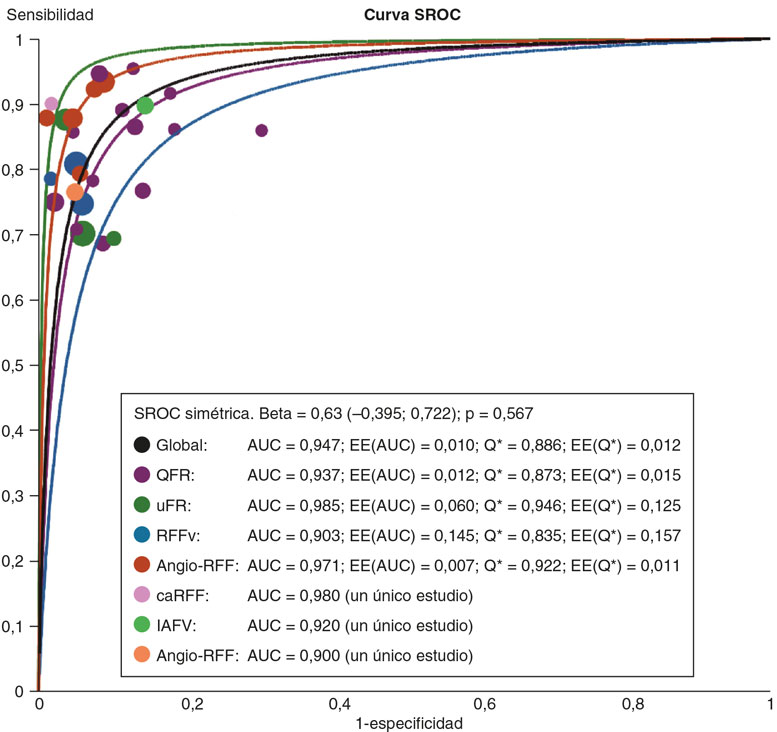

Técnicas de evaluación fisiológica derivadas de la angiografía: ¿todavía tienen cabida después de la publicación del ensayo FAVOR III Europe?

Artículos originales

Artículos de revisión